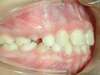

Intra Orale Droite